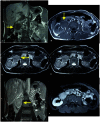

Castleman's disease (CD) is a rare lymphoproliferative disease of uncertain etiology that affects lymph nodes. CD can be classified as a) unicentric vs. multicentric, based on clinical and radiological findings, b) hyaline vascular (80-90%) vs. plasmacytic (10-20%) vs. mixed cellularity variety based on histopathology. Unicentric disease is more common in the 3rd and 4th decade, whereas the multicentric form is more common in the 5th and 6th decade with no sex predilection. HIV seropositive individuals appear to be at an increased risk for multicentric castleman's disease (MCD) at a younger age due to the increased incidence of HHV- 8 infection. Diagnosis is usually based on histopathology features as imaging features show considerable overlap, thus posing diagnostic difficulties. Overall prognosis is good, particularly in the unicentric variety of disease. We have presented a case of the unicentric CD in a 40 year old male patient having abdominal pain and hematuria as chief complaints.